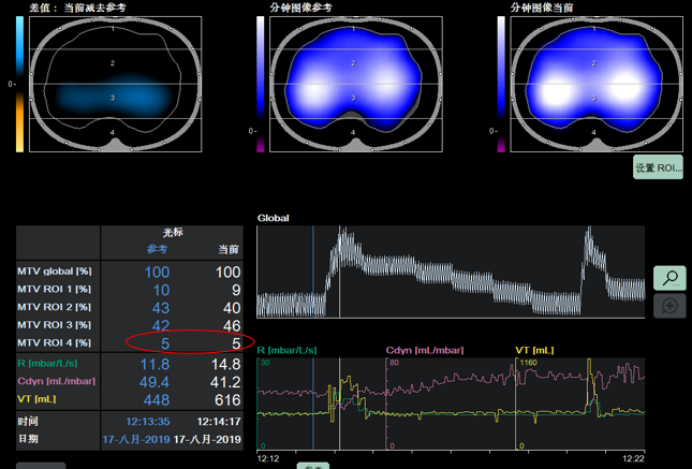

EIT技术能够在自主呼吸试验(SBT)期间,对潮气量的空间分布进行可视化呈现与定量化分析。GI升高或EELV下降(提示肺塌陷发生)时,可作为预测SBT失败的指标。如图3所示,在实施肺复张操作前后,肺部通气状况呈现出显著差异,借助EIT可清晰捕捉并直观展现这种变化,为评估肺复张效果、指导呼吸治疗提供有力依据。

图片

3  肺复张前后肺部通气的分布情况

评估肺的可复张性,可通过对比两个不同时间点潮气图像的阻抗差值实现。将差值以图像形式呈现(差值图像)4,能够精准判别肺内通气阻抗变化的部位,明确是哪些区域的阻抗增加(提示通气改善等可能),又或是哪些区域的阻抗减少(可能存在肺塌陷等情况),从而为判断肺复张效果、分析肺通气功能状态提供直观依据。

4  阻抗差值图像

肺可复张性评估参考流程如下:①设置ROI:采用分层模式,将肺部分为腹侧与背侧区域;②实施肺复张并对比分析:在实施肺复张操作后,对比复张前与复张过程中的肺通气分布状态,核心评估指标为通气分布的均一性是否改善;③判定可复张患者:对于背侧区域(ROI 4)的通气量较复张前出现明显增加的患者,可判定为具备可复张性的患者。图5-7所示为经EIT评估的肺可复张性。

5  有可复张性

6  部分可复张性

7  无可复张性